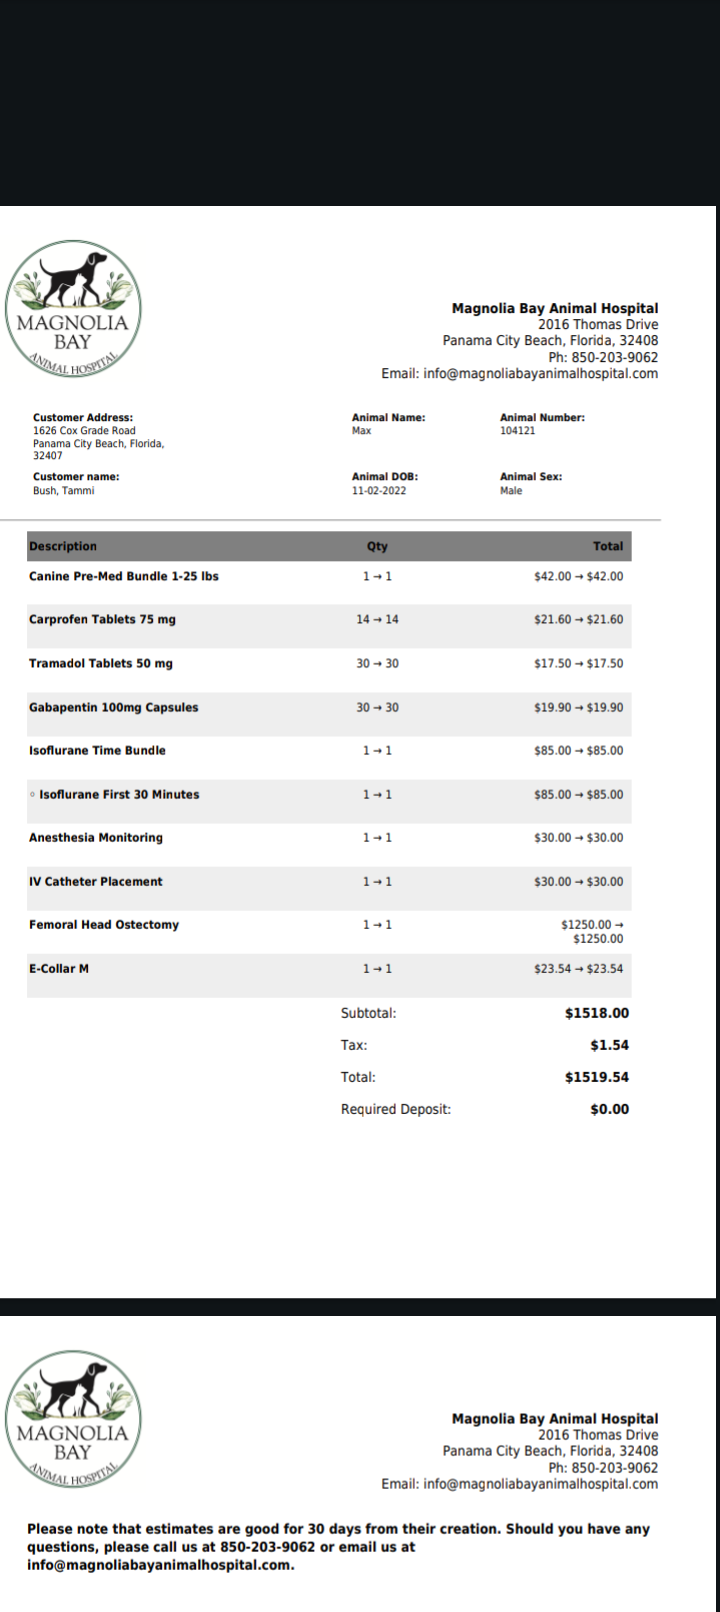

Max had his vet visit on Friday. The X-ray shows that his back leg joint has been displaced. Unfortunately, we can just "pop it back in". It requires surgery to get it fixed. I have attached the quote for that service as well. The Dr did say this is better than an actual break though, as it's not as painful as a broken bone would be. Also a broken bone would be much more expensive to fix. If you would like to help me you can donate several ways. You can call the vet listed on the estimate and make a payment on his behalf. You can send it directly to me. I have Venmo and Cashapp! I have also started a GofundMe on his behalf. Please help if you can! Pray for us if you don't mind! He has been taking medicine and antibiotics for the surface abrasions. He has pain medicine and anti-inflammatory. So far I have spent $375 dollars on vet bills and medicine. Another at least $1,500 to go. Thank you to those who have donated so far and thank you for those who are donating now! I'll never forget the ones who helped me in this time of need!